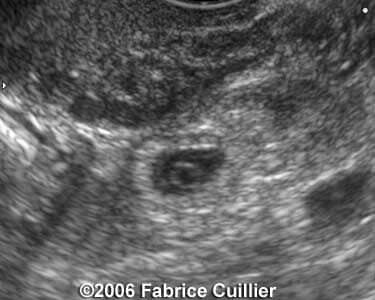

These are some cases of ectopic pregnancy (GEU) using the 2D and 3D scans.

Case 2